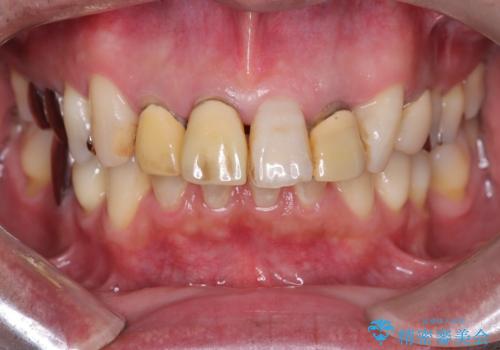

- 「被せ物の色が気になる」を主訴に来院された患者さんです。

保険で治療した被せ物が劣化し色も変色をおこしていました。かつ被せ物と歯の境目(適合)も合っていない状態でした。

被せ物の適合が悪く劣化もおこし色が変色している状態でした。そのため他の歯とも色が合っていませんでした。古い被せ物を除去し形を整えた後にオールセラミッククラウンで治療を行いました。